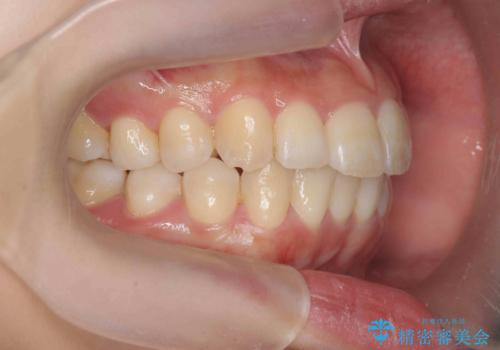

インビザラインで出っ歯の治療

- 「目立つ前歯の出っ歯をなんとかしてほしい。」と矯正治療を希望され来院されました。

突出した上顎の前歯に加え、ガタつきの目立つ下顎の歯列も同時にマウスピース矯正インビザラインで整えていきます。

突出間(所謂 出っ歯)のある前歯の位置は大幅に改善され、審美性が大きく向上しました。

加えて奥歯も噛み合わせも良くなったことで、咬合状態が安定しより安定した歯列を獲得することができました。